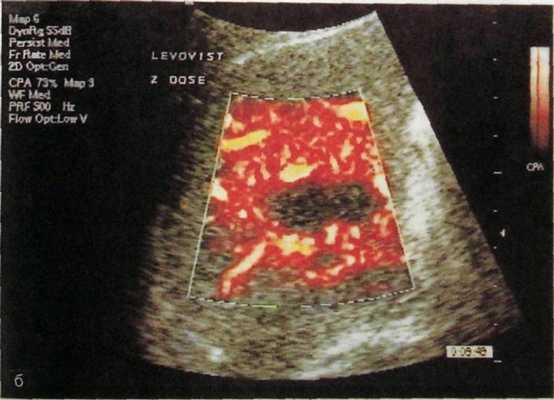

Среди всех средств визуализации метастазов наилучшим пространственным разрешением обладает КТ, особенно при ее выполнении по усиленной методике, далее следует МРТ и замыкают названную выше группу сонография и сцинтиграфия (рис. III. 143).

Рис. III. 143. Метастазы рака в печени.

а — компьютерная томограмма: множественные метастазы опухоли в печени; б — ультразвуковая ангиограмма: одиночный аваску-лярный метастаз в печени.